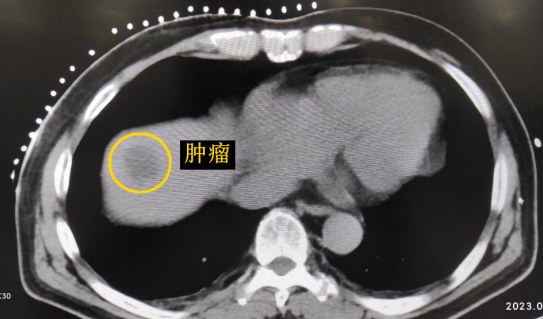

影像診療科陳寶瑩主任團(tuán)隊(duì)評估后指出,較大的腫瘤位于肝頂部緊貼膈肌,如果繼續(xù)發(fā)展,腫瘤很可能突破肝包膜侵犯到膈肌,建議及時(shí)干預(yù)。病變緊臨膈肌,如果要完全消融,膈肌損傷的可能性就比較大,與其他局部治療方式比較,冷凍消融對周圍臟器、血管及神經(jīng)損傷的可能性較小、安全性更高、患者疼痛感較輕,建議通過CT精準(zhǔn)引導(dǎo)下經(jīng)皮微創(chuàng)冷凍消融治療。

這個(gè)患者病變位置刁鉆,穿刺難度大,冷凍消融的難點(diǎn)在于既要不損傷膈肌和肺組織,同時(shí)又要盡最大可能完全消融腫瘤。術(shù)前陳寶瑩主任、李鐵柱教授、兀云飛醫(yī)生詳細(xì)設(shè)計(jì)進(jìn)針路徑、布針計(jì)劃,術(shù)中微創(chuàng)團(tuán)隊(duì)協(xié)調(diào)配合,李鐵柱教授仔細(xì)操作,精準(zhǔn)到位,順利完成兩個(gè)病變的布針,遂啟動(dòng)治療,先快速降溫到-150多度,再升溫至15?,經(jīng)過兩個(gè)循環(huán)反復(fù),即刻觀察到病變完全被冰球覆蓋,同時(shí)周圍臟器無損傷,術(shù)中患者幾乎沒有疼痛,還和醫(yī)生聊起了天。

CT精準(zhǔn)定位腫瘤